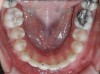

Fig 16. Occlusal view of patient shows the difference in angulation between the affected and the adjacent incisors.

Figure 16